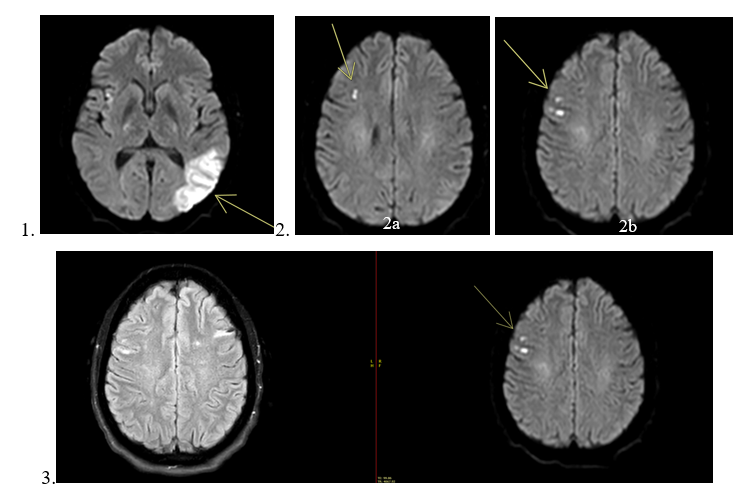

A non-contrast computed tomography (CT) of the head was negative for an acute intracranial hemorrhage. However, a magnetic resonance image (MRI) revealed an acute left occipitotemporal lobe infarct (Figure 1) in addition to a cluster of subacute infarcts in the lateral right frontal lobe (Figures 2a, 2b and 3). The distribution of these infarcts raised suspicion for an embolic etiology.

Figures 1, 2, and 3 are axial diffusion-weighted images (DWI) from the patient’s MRI. Figure 1 demonstrates the new left occipitotemporal infarct, while Figures 2a and 2b show the subacute infarcts in the lateral right frontal lobe. Figure 3 presents the DWI and FLAIR images for the subacute infarcts in the right frontal lobe.